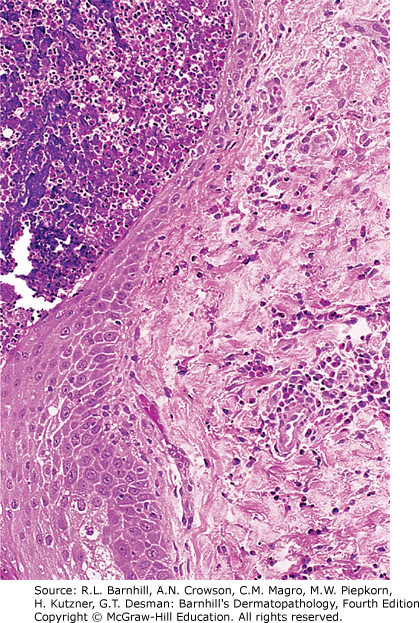

C. Fungal folliculitis is typically caused by Malassezia spp and can show budding yeasts within the hair follicle as seen below.